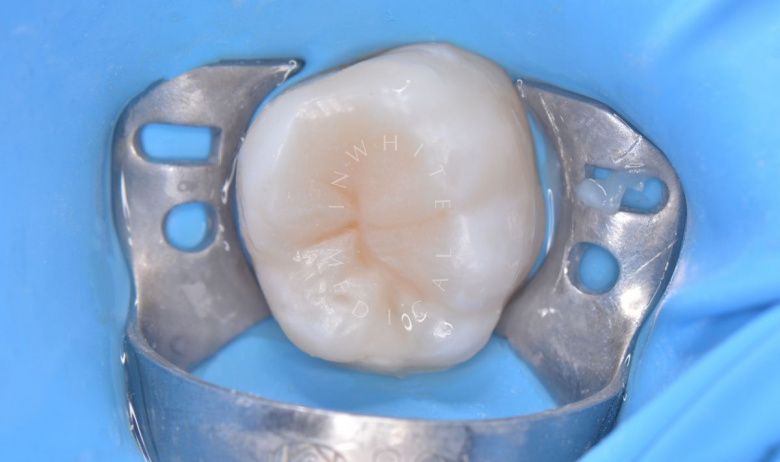

Результат

етская стоматология под наркозом Москва. Лечение молочных зубов и установка металлических коронок во сне - после процедуры